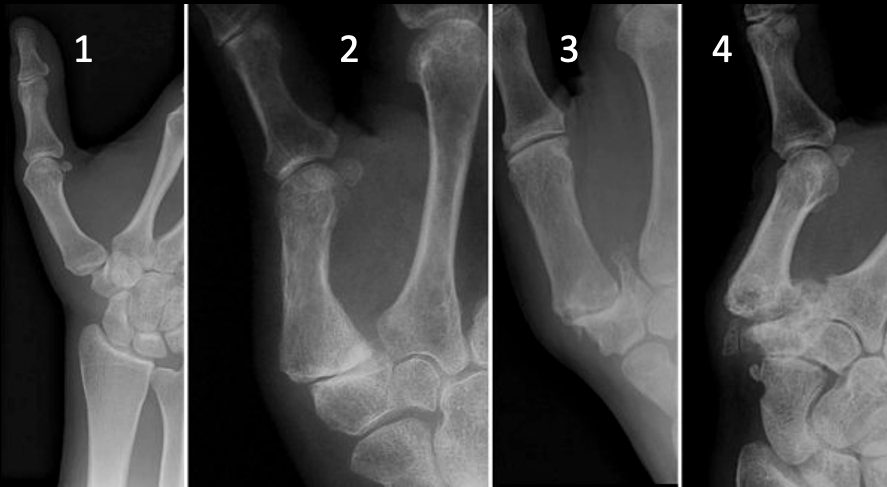

Classificação de Eaton Littler

Eaton Littler Radiográfica (perfil absoluto da TM) = sesamóides superpostos